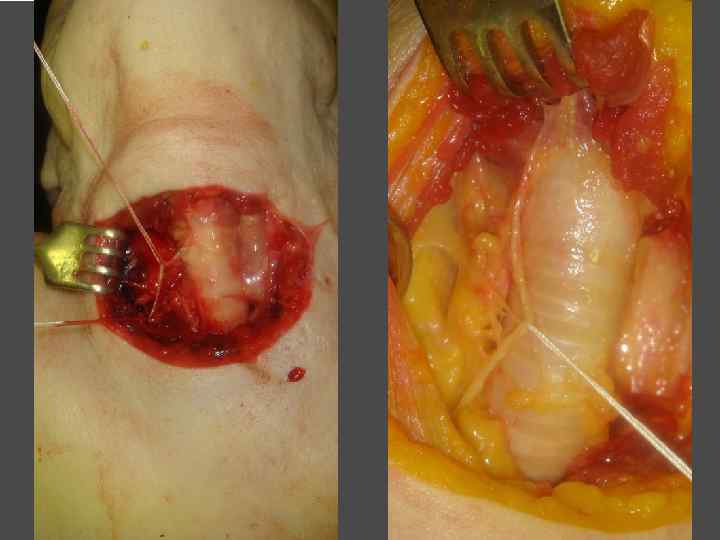

ХИРУРГИЧЕСКОЕ ЛЕЧЕНИЕ ЗОБА

ВИДЫ ХИРУРГИЧЕКИХ ВМЕШАТЕЛЬСТВ ► Энуклеация ► Резекция щитовидной железы (доли) ► Тиреоидэктомия (гемитиреоидэктомия)

ХИРУРГИЧЕСКОЕ ЛЕЧЕНИЕ ЗОБА

ОСЛОЖНЕНИЯ ХИРУРГИЧЕСКОГО ЛЕЧЕНИЯ ►Поражение возвратного нерва, приводящее к параличу голосовой связки на стороне поражения, как следствие – изменение тембра голоса, сужение голосовой щели, затруднение дыхания. ► Кровотечение. ►Тиреотоксический криз. ► Гипопаратиреоз. ► Рецидив тиреотоксикоза. ► Формирование порочного рубца.